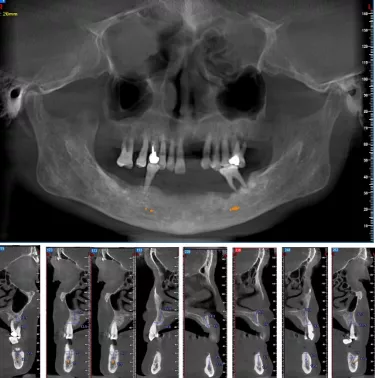

- CBCT示:21、22、27、31-33、35-37、41-45、47缺失,余牙牙槽骨吸收至根尖1/3。牙周膜间隙增宽。剩余牙槽骨丰满度一般。

CBCT检查见上下颌骨量